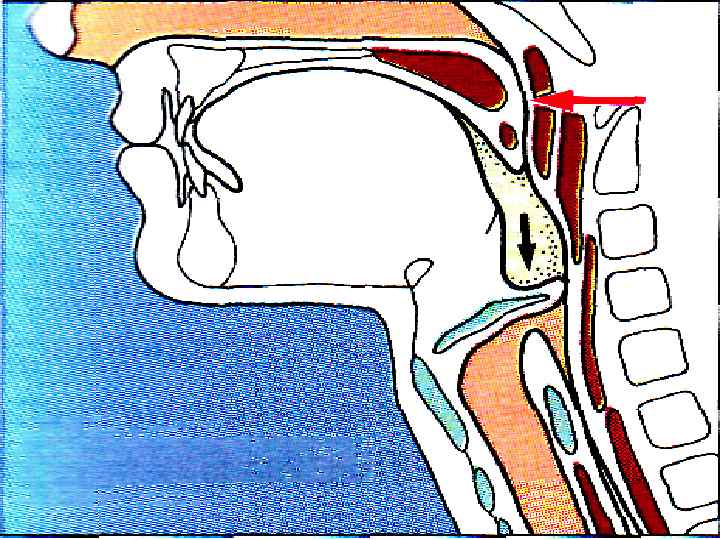

ФАЗЫ ГЛОТАНИЯ РОТОВАЯ (ПРОИЗВОЛЬНАЯ) ГЛОТОЧНАЯ ПИЩЕВОДНАЯ

ФАЗЫ ГЛОТАНИЯ РОТОВАЯ (ПРОИЗВОЛЬНАЯ) ГЛОТОЧНАЯ ПИЩЕВОДНАЯ

ГЛОТОЧНАЯ ФАЗА

ГЛОТОЧНАЯ ФАЗА

1. МЯГКОЕ НЕБО ЗАКРЫВАЕТ ХОАНЫ 2. НЕБНО-ГЛОТОЧНЫЕ СКЛАДКИ – САГИТТАЛЬНУЮ ЩЕЛЬ 3. ГОЛОСОВАЯ ЩЕЛЬ СМЫКАЕТСЯ, ГОРТАНЬ ПОДТЯГИВАЕТСЯ ВВЕРХ → НАДГОРТАННИК – КЗАДИ

1. МЯГКОЕ НЕБО ЗАКРЫВАЕТ ХОАНЫ 2. НЕБНО-ГЛОТОЧНЫЕ СКЛАДКИ – САГИТТАЛЬНУЮ ЩЕЛЬ 3. ГОЛОСОВАЯ ЩЕЛЬ СМЫКАЕТСЯ, ГОРТАНЬ ПОДТЯГИВАЕТСЯ ВВЕРХ → НАДГОРТАННИК – КЗАДИ

4. ПИЩЕВОД – ВВЕРХ, ВХОД РАСШИРЯЕТСЯ 5. ВЕРХНИЙ ПИЩЕВОДНЫЙ СФИНКТЕР РАСКРЫВАЕТСЯ 6. ГЛОТКА СОКРАЩАЕТСЯ, ПРОТАЛКИВАЯ ПИЩУ t=2 c

4. ПИЩЕВОД – ВВЕРХ, ВХОД РАСШИРЯЕТСЯ 5. ВЕРХНИЙ ПИЩЕВОДНЫЙ СФИНКТЕР РАСКРЫВАЕТСЯ 6. ГЛОТКА СОКРАЩАЕТСЯ, ПРОТАЛКИВАЯ ПИЩУ t=2 c